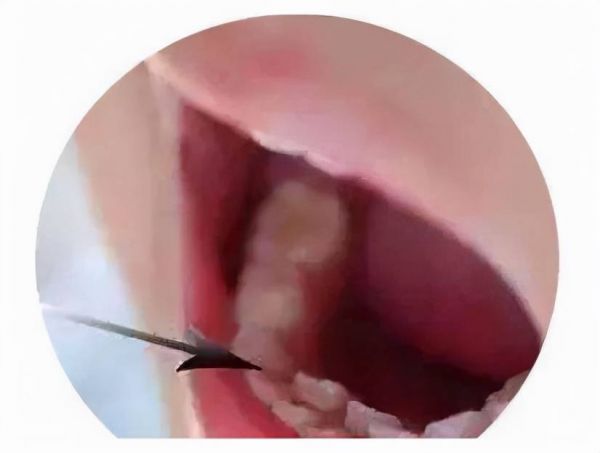

▼乳牙滞留出现双排牙

恒牙已经萌出到位,但是乳牙依旧没有脱落,肉眼视觉上看孩子长了“双排牙”,在医学上的专业解释则是“乳牙滞留”。

造成这一现象的原因,少数是因为天生恒牙出位异常、恒牙天生缺失有关,更多的则是因为现代儿童普遍存在饮食过于精细,存在咀嚼不足的现象。乳牙未曾发挥应有的咀嚼功效,没有得到锻炼和刺激,从而让孩子出现了乳牙滞留。

要避免乳牙滞留的问题,除了日常生活中要让孩子多锻炼咀嚼能力之外,一旦发现有乳牙滞留的现象出现,不能抱着“等一等”的心态拖延,务必及时到口腔医院就诊。在专业医生安排下拔除乳牙,让恒牙生长不受影响。